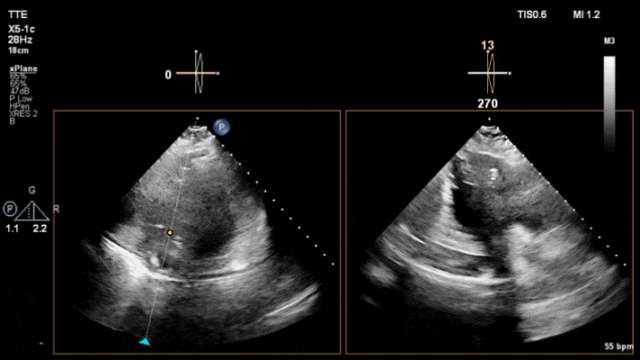

Video1:心尖四腔心切面(双平面)引导下调整无导线起搏器递送系统头端贴靠室间隔并给予一定的张力使递送系统在右心室内形成凸向游离壁的弧度(相当于X线下的“鹅颈征”)